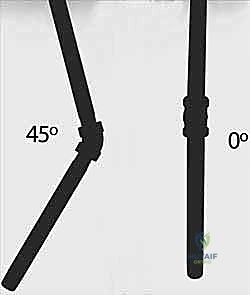

Age-dependent angulation limits are the primary drivers for surgical decision-making. In children under 8 to 10 years of age, greater than 20 degrees of angulation in the distal third, greater than 15 degrees in the central third, and greater than 10 degrees in the proximal third are generally unacceptable. For children over 10 years of age, the tolerance is much lower; generally, no more than 10 degrees of angulation is acceptable at any level due to the diminished remodeling potential. Furthermore, rotational malalignment exceeding 30 to 45 degrees is an absolute indication for correction, as it will not remodel and will result in a permanent mechanical block.

An awl or a drill bit (slightly larger than the selected nail diameter) is used to breach the near cortex. The entry angle is critical; it must begin perpendicular to the bone to prevent skiving, then gradually angle to approximately 45 degrees relative to the shaft axis to facilitate smooth nail passage into the medullary canal.

The awl is introduced just proximal to the physis, again starting perpendicular and angling proximally.